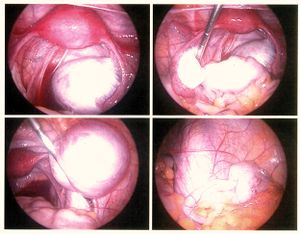

- عملية التنظير البطني: يعتبر من أهم الوسائل التشخيصية لهذا المرض حيث وجد أن 50% من النساء اللاتي لديهن الم أثناء الدورة الشهرية وألم في الحوض مصابات بداء البطانة الرحمية الهاجرة عند إجراء عملية التنظير.

- المنظار البطني لغرض إزالة البطانة الهاجرة بواسطة الحرارة أو الليزر وإزالة الالتصاقات و أكياس الدم وغالبا ما يستخدم عندما تكون المرأة في سن الخصوبة وترغب بإنجاب الأطفال.